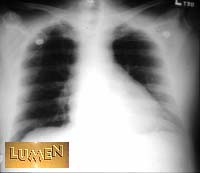

Which X-ray was taken A-P?

Notice the heart size.